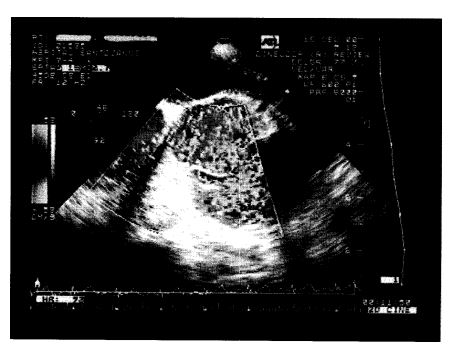

Los aneurismas congenitos del seno de Valsalva (ASV) son el resultado de una dilatacion en la zona de union de la capa media aortica con el anillo fibroso de la valvula aortica causada por la action de la presion arterial sobre un punto debil de la pared y es frecuente su perforation hacia las cavidades derechas. Se presenta el caso de una mujer de 28 anos, con ASV roto hacia el tracto de salida del ventriculo derecho (TSVD), presumiblemente por endocarditis infecciosa, que evoluciona con insuficiencia cardiaca congestiva (ICC) y muerte.